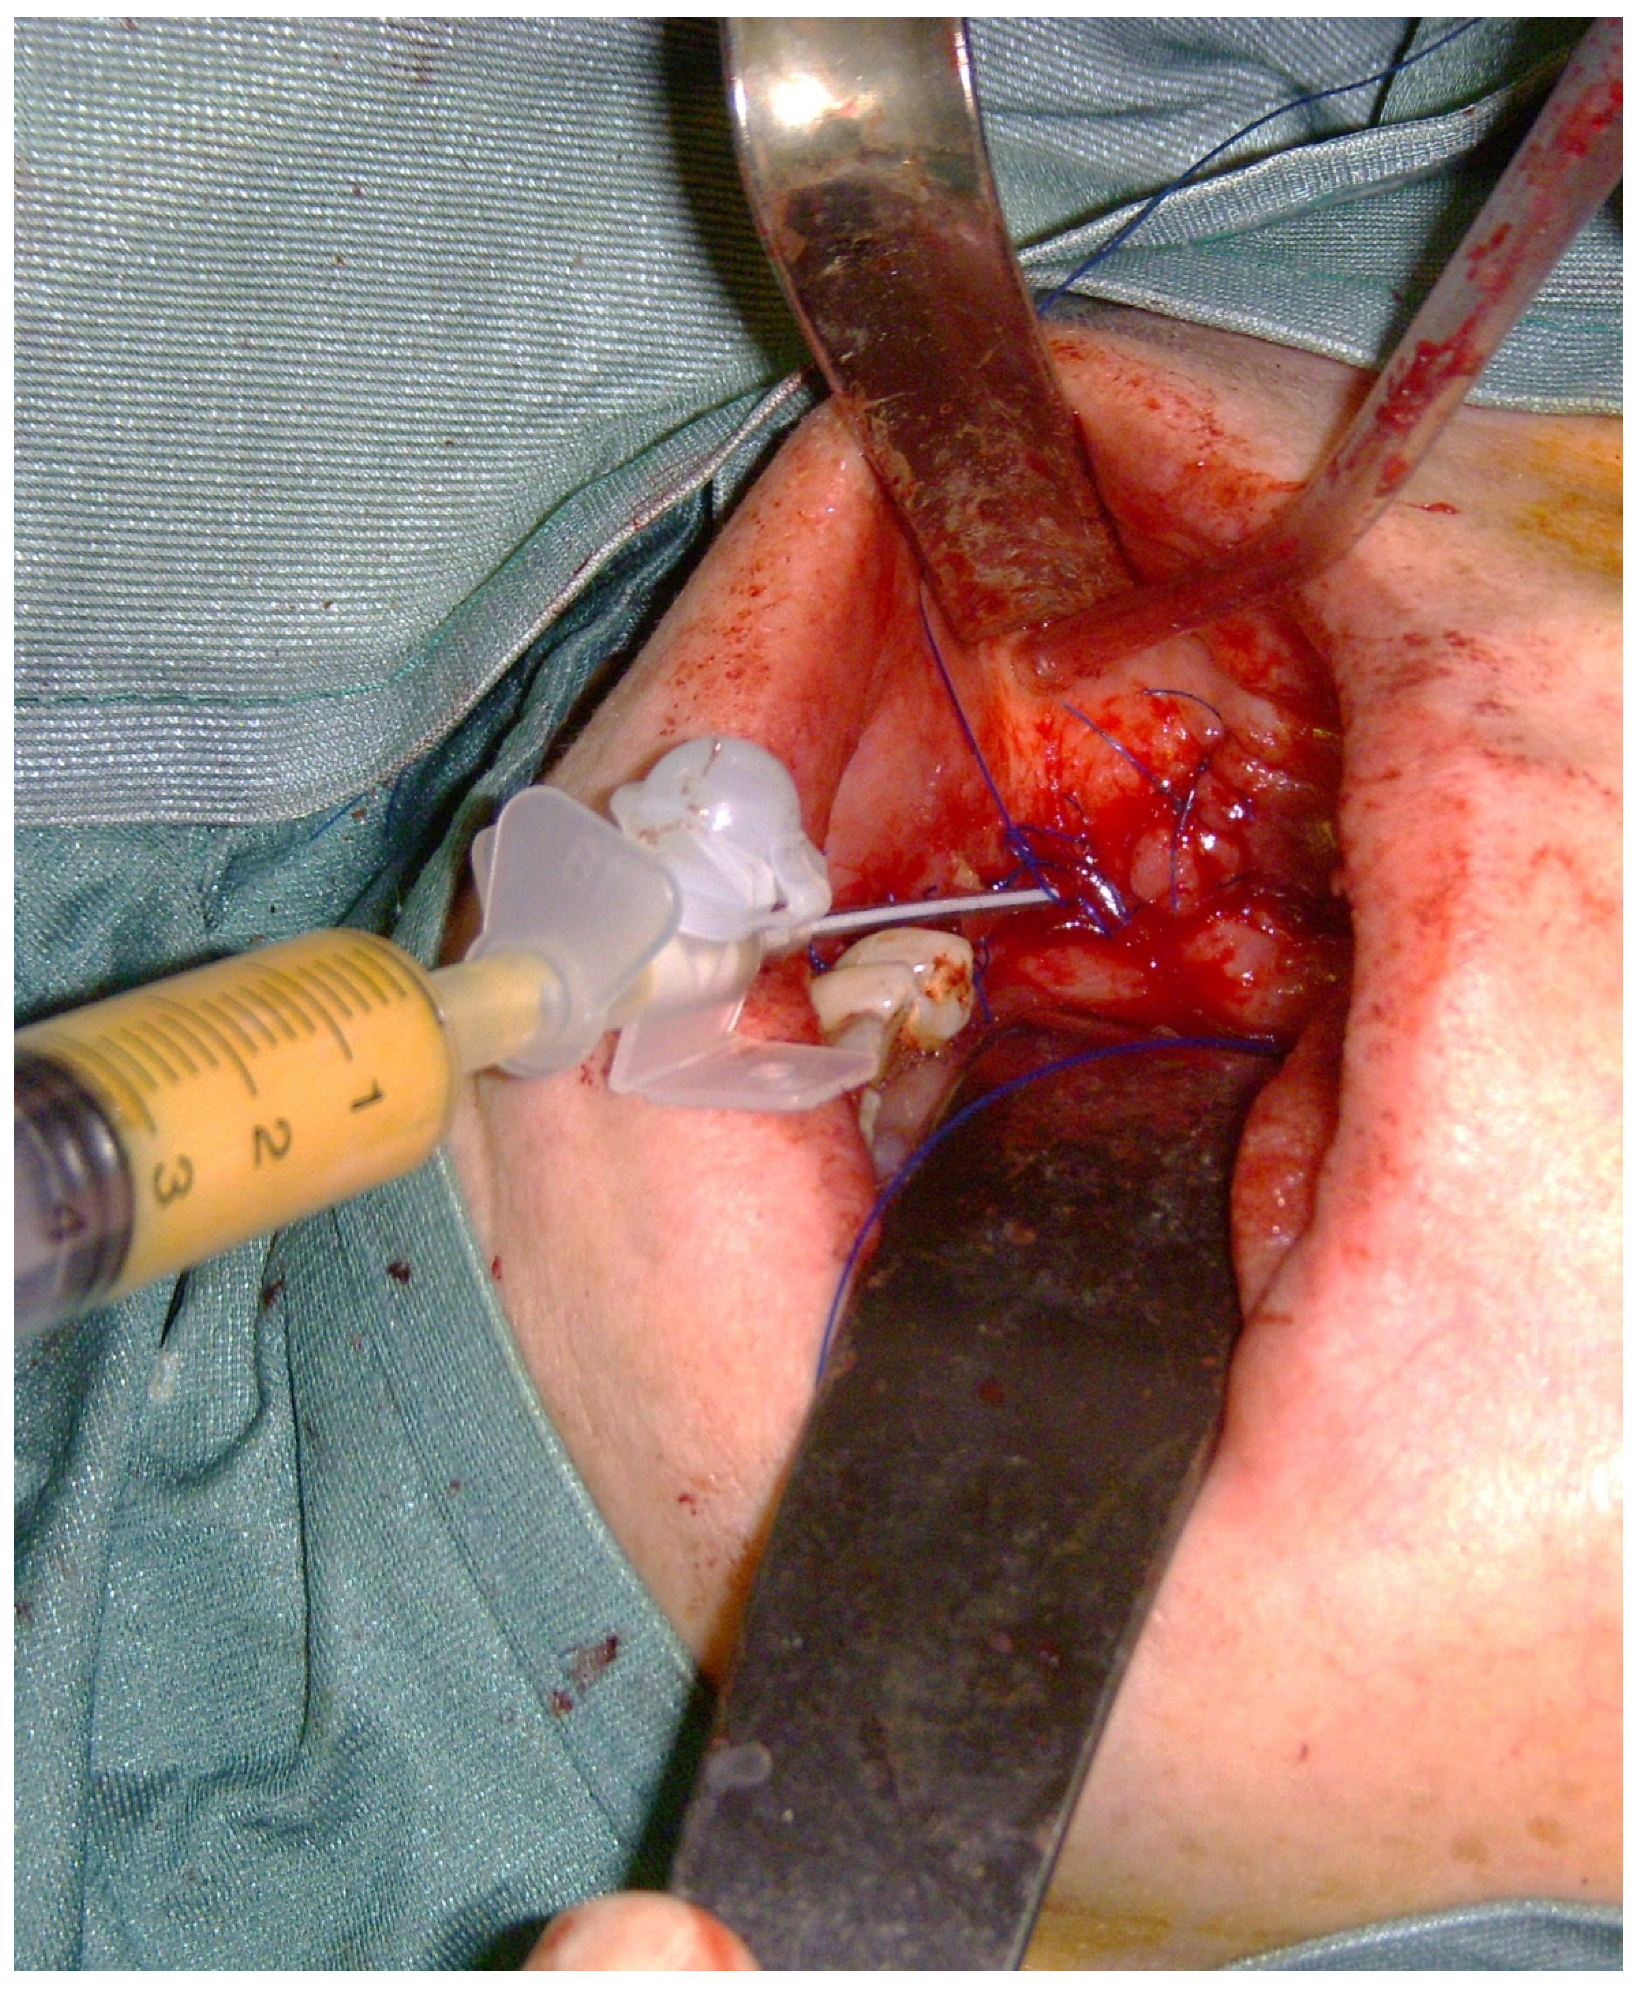

2. Materials and Methods

- Group A (n = 9)—patients who received sequestrectomy and autologous fat graft;

- Group B (n = 12)—patients who received sequestrectomy alone.

Treatment Protocol